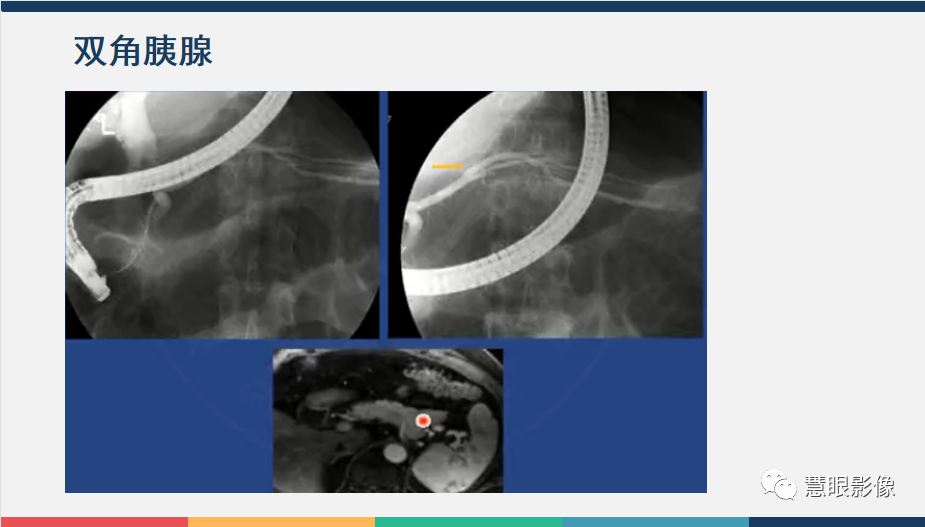

【PPT】胰腺解剖变异、发育异常及相关病变影像评估-2